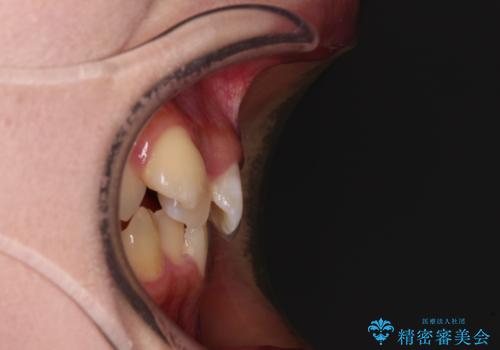

- 上下の八重歯を気にして来院された患者様です。

非抜歯矯正で歯列を整えると、治療後に口元が今よりも突出する可能性が高かったため、上下左右の小臼歯4本を抜歯し、ワイヤー装置にて矯正治療を行うこととしました。

右上の八重歯の影響で、右側は上顎歯列が前方位の咬み合わせとなってしまっていたため、上顎は第一小臼歯を、下顎は第二小臼歯を抜歯することで咬み合わせや上下正中を調整することとしました。